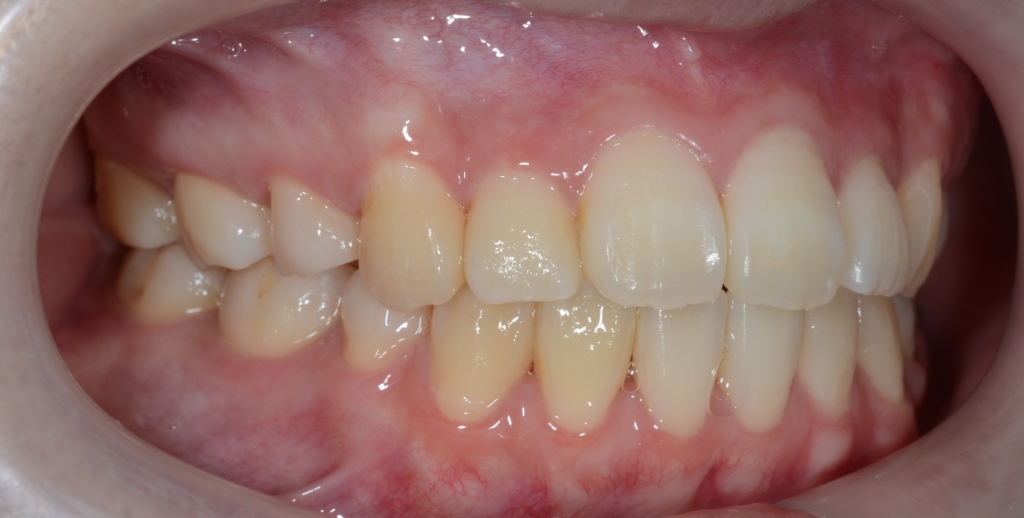

左側が矯正治療前、右側が矯正治療後